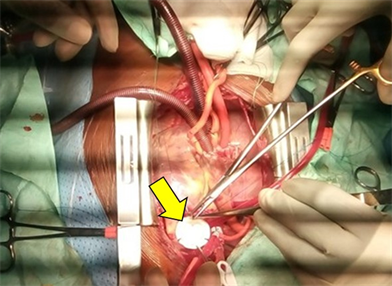

Thoracic computed tomography (Figure 1) showed pulmonary valve agenesis with proximal trunk stenosis of a pulmonary artery measuring 10 mm in the first portion, trunk aneurysmal dilatation in the second portion and dilatation of the pulmonary branches (35 mm for the right and 28 mm for the left). The aortic arch was in the right side. No sign of bronchial compression was seen.

Figure 1. Chest CT angiography shows: (a) Aorta in the right side (b) Pulmonary valve agenesis with proximal trunk stenosis of a pulmonary artery measuring 10 mm, trunk aneurysmal dilatation.